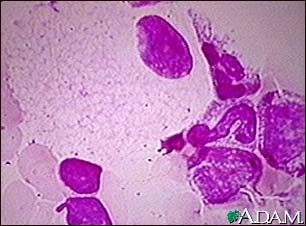

Болезнь Нимана-Пика Тип А: Симптомы и лечение

Раздел: Визуальный дайджест